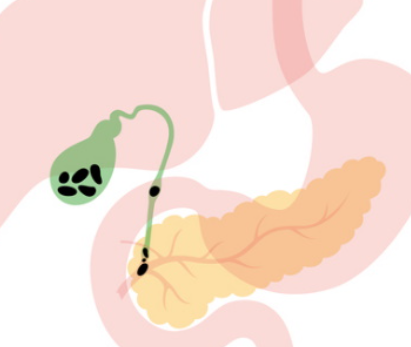

담낭염은 담낭의 벽에 염증이 발생하는 질환으로, 이는 대부분 담석증 때문에 발생합니다. 담석증이란 담즙에 포함된 콜레스테롤이나 빌리루빈 같은 물질이 응고되어 돌처럼 굳어진 상태를 말하며, 이러한 담석이 담낭의 출구를 막게 되면 담즙이 제대로 배출되지 못하고 담낭 내에 고이게 됩니다.

이 상태가 지속되면 담낭 내부의 압력이 증가하게 되고, 이는 결국 염증을 유발하게 됩니다. 염증이 진행됨에 따라 담낭 벽이 두꺼워지고, 이 상태가 심해지면 감염으로 이어질 수도 있습니다.